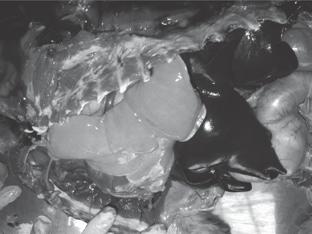

Disección fina.  En los tres especímenes se  logró obtener un árbol bronquial completo, previa fijación de éste en formol al 10%  durante 48 horas  (Figura 3). Así mismo,  el corte  coronal de los pulmones en un espécimen permitió comparar la distribución bronquial de la disección fina con la obtenida en cada  lóbulo (Figura 4).

Figura 4.  Corte coronal del pulmón, vista ventrodorsal, se definen claramente cada una de las divisiones de los bronquios intrapulmonares

Bronquios lobulares. Los bronquios lobulares excepto en el lóbulo apical izquierdo mostraron una porción intrapulmonar larga y una extrapulmonar corta. Las porciones craneal y caudal del lóbulo apical izquierdo tienen su origen en un bronquio lobular común y no mostraron porciones extrapulmonares. El bronquio común era totalmente extrapulmonar (Figura 4).